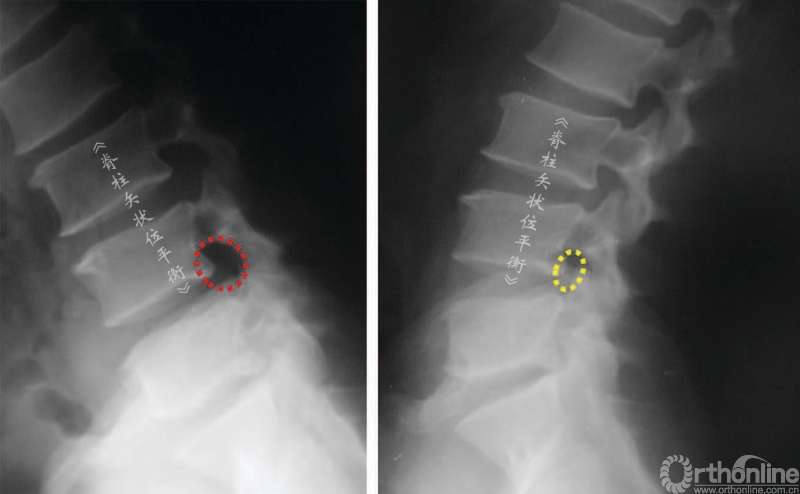

骨关节炎性的椎管狭窄导致伸展时(或前凸)比屈曲时(或后凸)出现更多的症状。不考虑椎管水平因素时,椎管前后径伸展时减小,屈曲时增大。同时,根据神经根的运动原理,神经根屈曲时向椎体前方运动靠近椎体和椎间盘,伸展时向后运动靠近后方椎弓(图8,图9)。

这也解释了颈椎伸展时会加剧压迫性、骨关节炎的颈、臂部的疼痛症状,腰椎屈曲或后凸时可改善腰椎管狭窄引起的神经源性跛行。伸展站立位X线不注射或注射造影剂(脊髓造影术)可证明这种动态受压的过程(图9,图10)。

脊柱后凸会挤压神经引起相应的症状,多见于腰椎管狭窄症。间歇性跛行是继发于椎管狭窄的一种临床症状,在处于伸展位置时加重。一些矢状位失平衡患者可以通过简单的神经根减压术改善其平衡状态。

图8 神经根位移,屈曲(A) 和伸展(B)时椎管容积改变

图9 屈曲(A)和伸展(B)时椎间孔的比较

图10  L3~L4 和L4~L5中央椎管体积减小,伸展位(B)和屈曲位(A)的比较